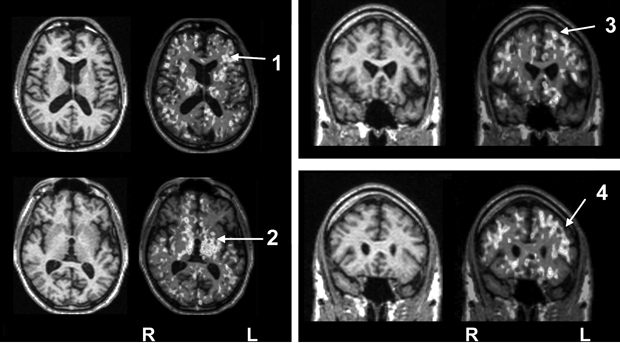

As discussed above, illness severity and prognosis can be based on biological measures that are not diagnostically specific. In this context, disease-induced microglial activation, which has been well established, can serve as a generic marker that relates more directly to disease progression.10,46-50 Preliminary studies in patients with schizophrenia suggest that microglial activation is present (Box 3) and may be correlated with other meaningful illness measures, such as (event-related potential derived) mismatch negativity.